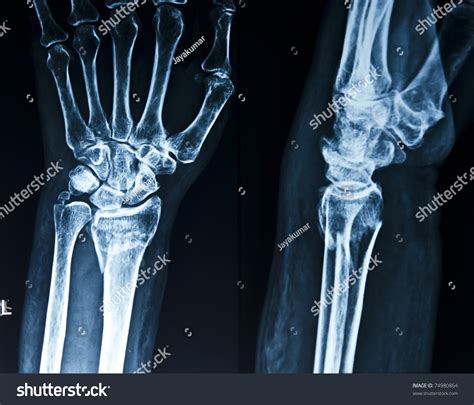

Injuries to the hand are quite common, and one of the most effective ways to diagnose and assess the extent of the damage is through a broken hand x-ray. This diagnostic tool provides a clear view of the bones and can help healthcare professionals determine the best course of treatment. Understanding the process, benefits, and what to expect from a broken hand x-ray can be incredibly helpful for anyone who finds themselves in this situation.

A broken hand x-ray is a type of medical imaging that uses low levels of radiation to produce images of the bones in the hand. These images are crucial for diagnosing fractures, dislocations, and other bone-related injuries. The x-ray machine emits X-rays that pass through the body and are absorbed differently by various tissues. Bones, being denser, absorb more X-rays and appear white on the resulting image, while softer tissues appear darker.